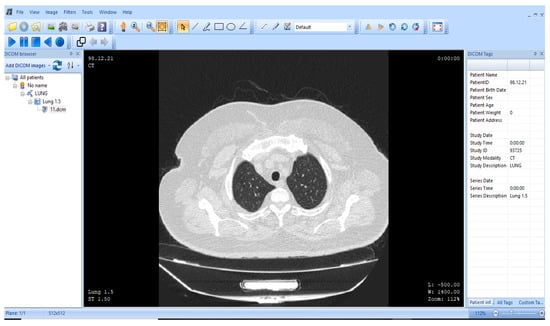

Figure 10 presents the view of the DICOM image under observation. MicroDICOM software (DICOM Viewer 2023) is used to analyze the DICOM image of the human body. The DICOM image has dimensions of . The “computed tomography (CT)” scan image used in this work shows a human lung. Since the proposed methodology is developed to be implemented on medical images, DICOM images are best suited for this application. The image compression of the DICOM is performed with the assistance of Matlab 2018 (b), with an operating system having a processor, and a hard drive.

Figure 10.

representation of the human lung (MicroDICOM) [85].